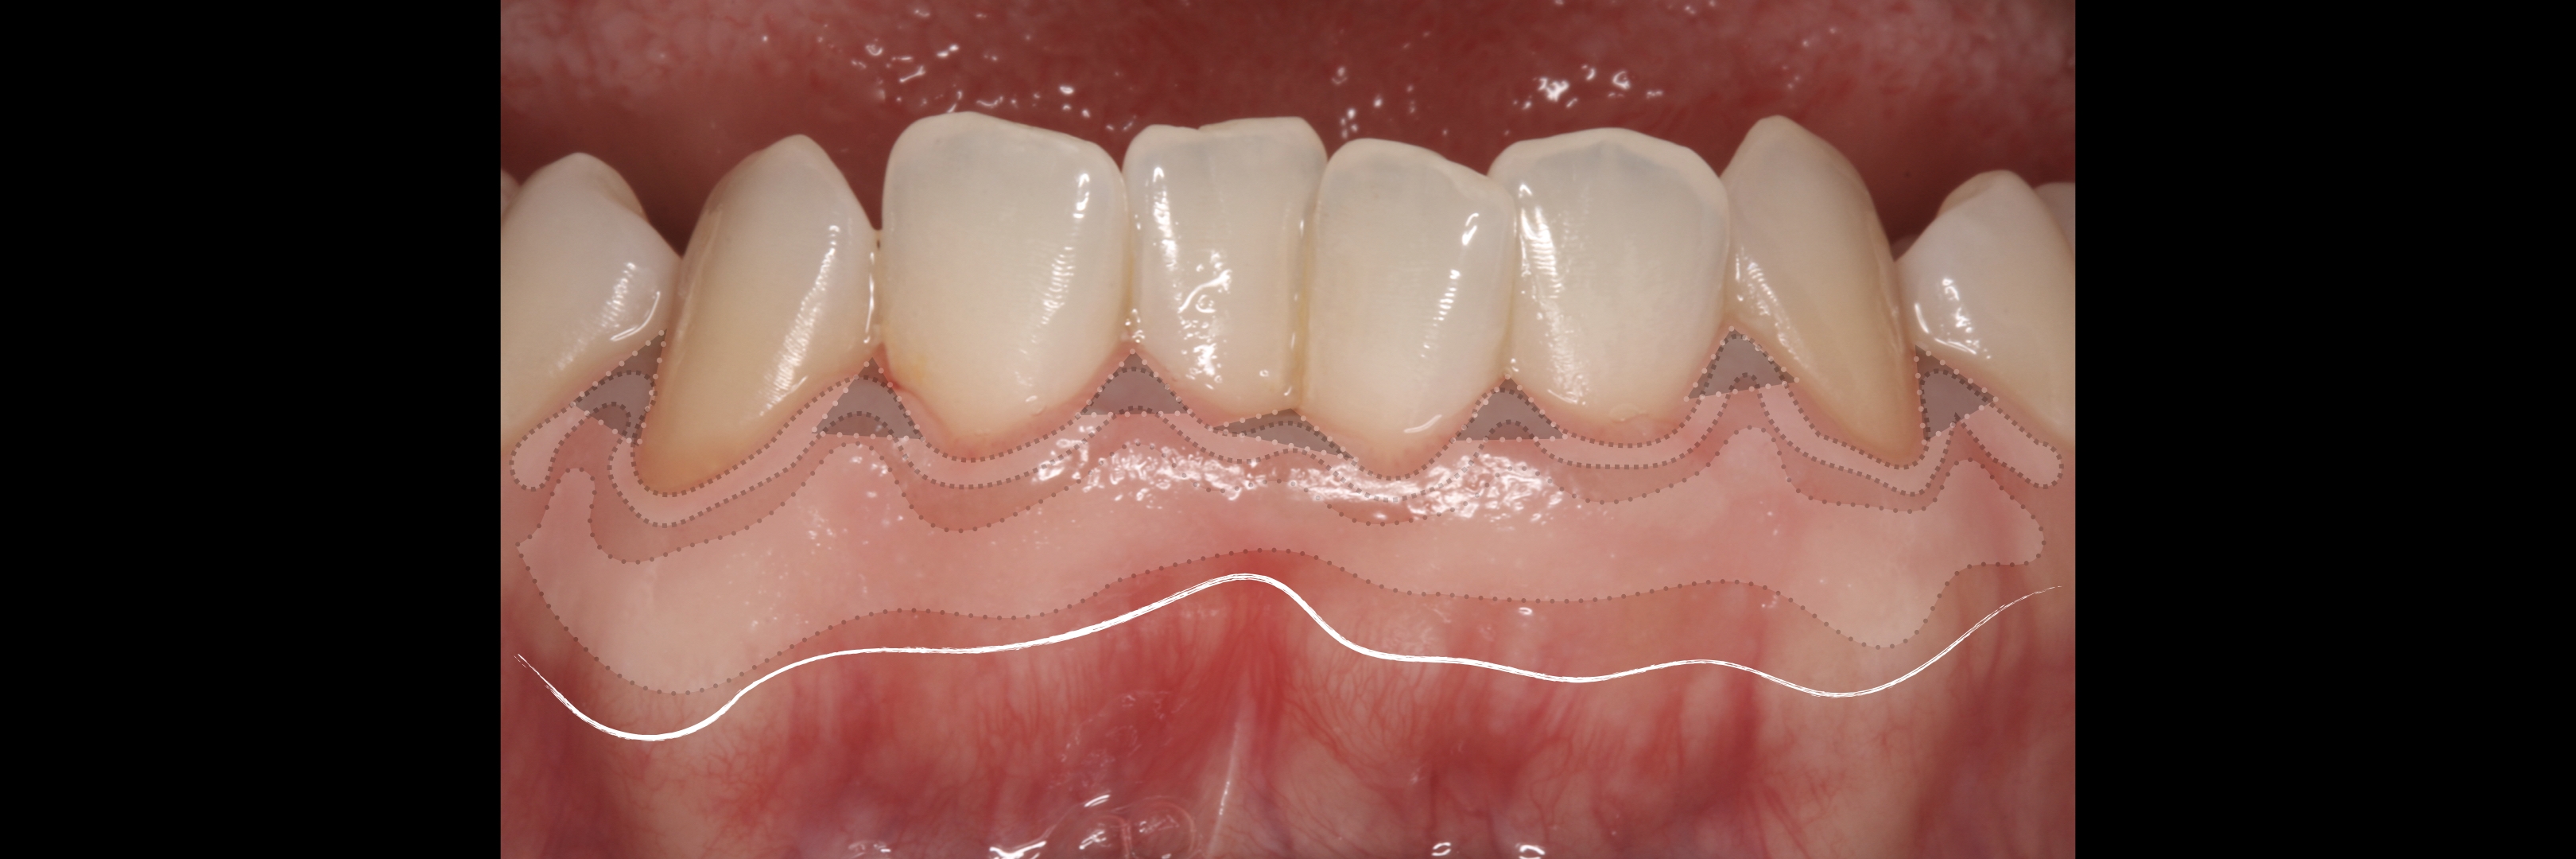

KERATINIZED gingiva includes

the free gingiva

(marginal gingiva & papillae)

and the attached gingiva extending from the gingival mar­gin to the mucogingival junction.

Generally we tend to forget about these 2 parameters, free and the attached gingiva are both essential parts of the keratinized gingiva.

This meaning that keratinized (load bearing capacity) is a mechanical characteristic that makes up for attached gingiva, providing it's immobility,  but also is of such importance as the thickness it provides around whatever perforates the epithelium, be it implants or teeth, being also keratinized (having load bearing capacity) at this location.

However free marginal gingiva is different in characteristics on its outer and inner surfaces: outer surface is keratinized;

inner surface is

non-keratinized, constituting part of the gingival sulcus.